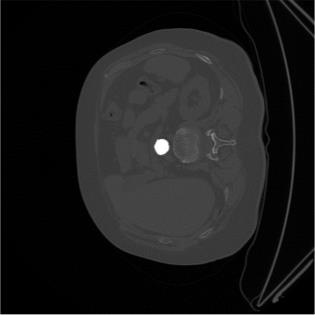

2D biomedical semantic segmentation is important for robotic vision in surgery. Segmentation methods based on Deep Convolutional Neural Network (DCNN) can out-perform conventional methods in terms of both accuracy and levels of automation. One common issue in training a DCNN for biomedical semantic segmentation is the internal covariate shift where the training of convolutional kernels is encumbered by the distribution change of input features, hence both the training speed and performance are decreased. Batch Normalization (BN) is the first proposed method for addressing internal covariate shift and is widely used. Instance Normalization (IN) and Layer Normalization (LN) have also been proposed. Group Normalization (GN) is proposed more recently and has not yet been applied to 2D biomedical semantic segmentation, however, no specific validations on GN were given. Most DCNNs for biomedical semantic segmentation adopt BN as the normalization method by default, without reviewing its performance. In this paper, four normalization methods - BN, IN, LN and GN are compared in details, specifically for 2D biomedical semantic segmentation. U-Net is adopted as the basic DCNN structure. Three datasets regarding the Right Ventricle (RV), aorta, and Left Ventricle (LV) are used for the validation. The results show that detailed subdivision of the feature map, i.e. GN with a large group number or IN, achieves higher accuracy. This accuracy improvement mainly comes from better model generalization. Codes are uploaded and maintained at Xiao-Yun Zhou's Github.